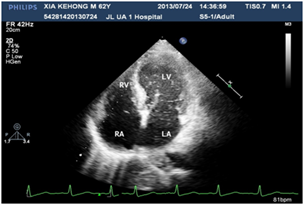

A 60years old male, known case of diabetes mellitus, hypertension and alcoholic hepatic cirrhosis had exercise induced chest discomfot, shortness of breath, fatigue and lips cyanosis half a year ago, which relieved at rest. But later he became serious for one week and visited our department for further management. He had no cough, fever, dizziness, headache or bleeding history from any site. He had pituitary adenoma, which was surgically removed 6years ago. He denies history of chronic infections such as tuberculosis or actinomycosis or family history of hereditary hemorrhagic telangiectasis (HHT). Physical examination revealed cyanosis of the face and lips, clubbing, numerous spider naevi on neck, chest and palm and no telangiectasia on mucosa or fundi. His blood pressure was 130/80mmHg, heart rate was 76beats/min and resting oxygen saturation was 66% in room air. A grade 1/6 soft systolic murmur was heard on the upper left sternal border and clear lungs sound. There were no bruits. The hemoglobin was 11.5gm/dL and the hematocrite was 35.5gm/dL. Arterial blood gas analysis showed Pao2 64mmHg on room air and after 100% of oxygen 74mmHg with Paco2 41mmHg and PH-7.35. Chest radiography and electrocardiogram did not show any abnormalities. Pulmonary function test showed alveolar dispersion function severely reduced. Transthoracic echocardiography showed normal findings (No PFO/ASD/VSD/PDA detected). We performed contrast echocardiography using agitated saline. A delayed appearance of a substantial amount of micro-bubbles in the left atrium greater than three cardiac cycles after appearance in the right atrium and ventricle (Figure 1) which was suggestive of pulmonary arteriovenous fistula. The delayed appearance and a large amount of micro-bubbles in the left atrium preclude the intracardiac shunting resulting from a patent foramen ovale (PFO) or arterial septal defect (ASD). Interestingly, the density of micro-bubbles was the same in the left and right cardiac chamber even after 10 cardiac cycles (Figure 2 & 3) and when the injection stopped, there were micro-bubbles in the left cardiac chambers meanwhile none in the right cardiac chambers (Figure 4). Because the hepatic function of the patient was in compensatory period, we gave him oxygen-inhalation and beta-blockers in order to decrease the oxygen demands and to lower the portal vein pressure. Moreover, he was advised to avoid sudden standing. The cyanosis improved, and the patient was discharged from the hospital and on regular follow-up. The patient was advised for pulmonary angiography but refused.

Figure 1 Micro-bubble appears in RA, RV, delayed appearance in LA, LV.